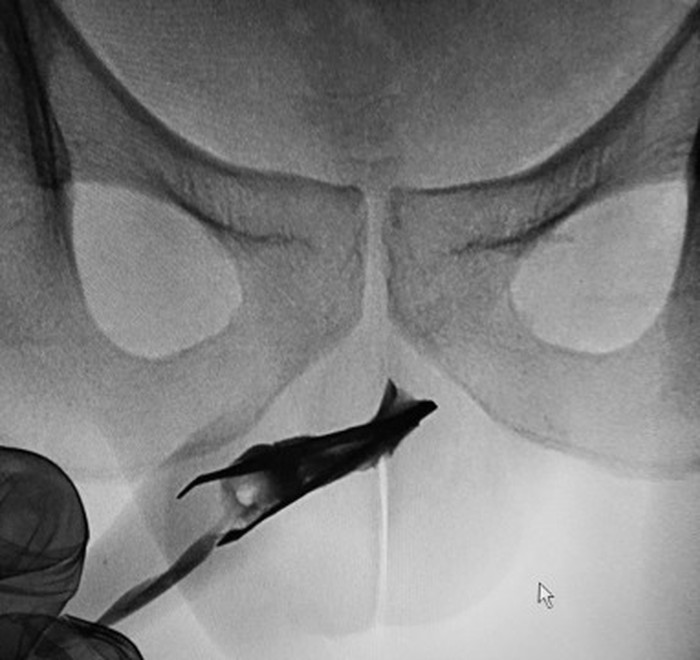

Seorang pasien pria berusia 22 tahun di Arab Saudi datang ke dokter karena kasus aneh. Ada sebuah pinset sepanjang 7 cm yang tersangkut di uretranya. (Foto: Urology Case Reports)

Diketahui, benda asing itu ia masukkan sendiri ke dalam penisnya sekitar empat tahun sebelum bertemu dokter. Temuan ini dilaporkan dalam laporan yang dipublikasi di Urology Case Reports. (Foto: Urology Case Reports)

Untuk mengeluarkannya, pasien diberikan anestesi umum dan menggunakan metode pemerasan yang mereka sebut 'teknik tekanan eksternal'. Setelah prosedur selesai, pasien dapat buang air kecil secara normal dan diperbolehkan pulang. (Foto: Urology Case Reports)